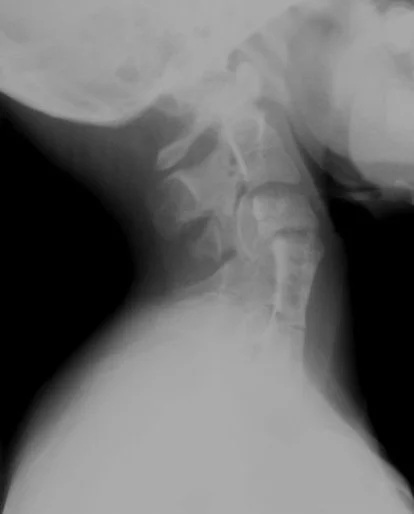

Left:

• Multilevel cervical fusion shown well

Right:

• Demonstrates left sided omnovertebral bone adjacent to C7-T3